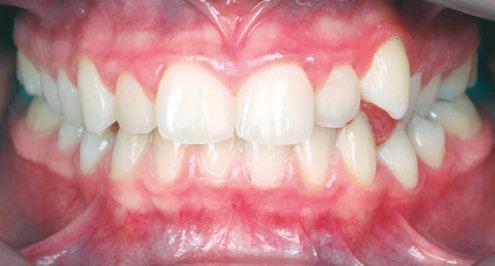

Drs. Claudia Pinter and Stanley Liu illustrate a protocol to improve nasal breathing in orthodontic care 31